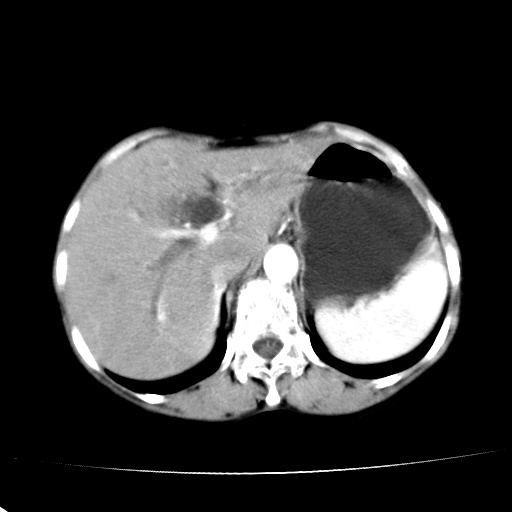

以下是引用jiangjing在2008-6-3 13:36:00的发言:[br]支持 胰头癌------肝内外胆管扩张,胰管扩张,胰头增大,增强见结节状轻度强化影,双管征明显

以下是引用卜一在2008-6-3 14:40:00的发言:[br]支持:胰头癌!(肝内外胆管扩张,胆囊高度扩张,胰管扩张,胰头增大,增强见结节状强化,明显低于胰腺强化密度,并明显见双管征)

以下是引用dyqct在2008-6-3 14:54:00的发言:[br]支持 胰头癌伴肝内外胆管扩张,胰管扩张,胰头增大,增强见结节状轻度强化影,双管征明显。肠系膜上静脉已受侵(已不能手术),建议离子植入治疗吧。